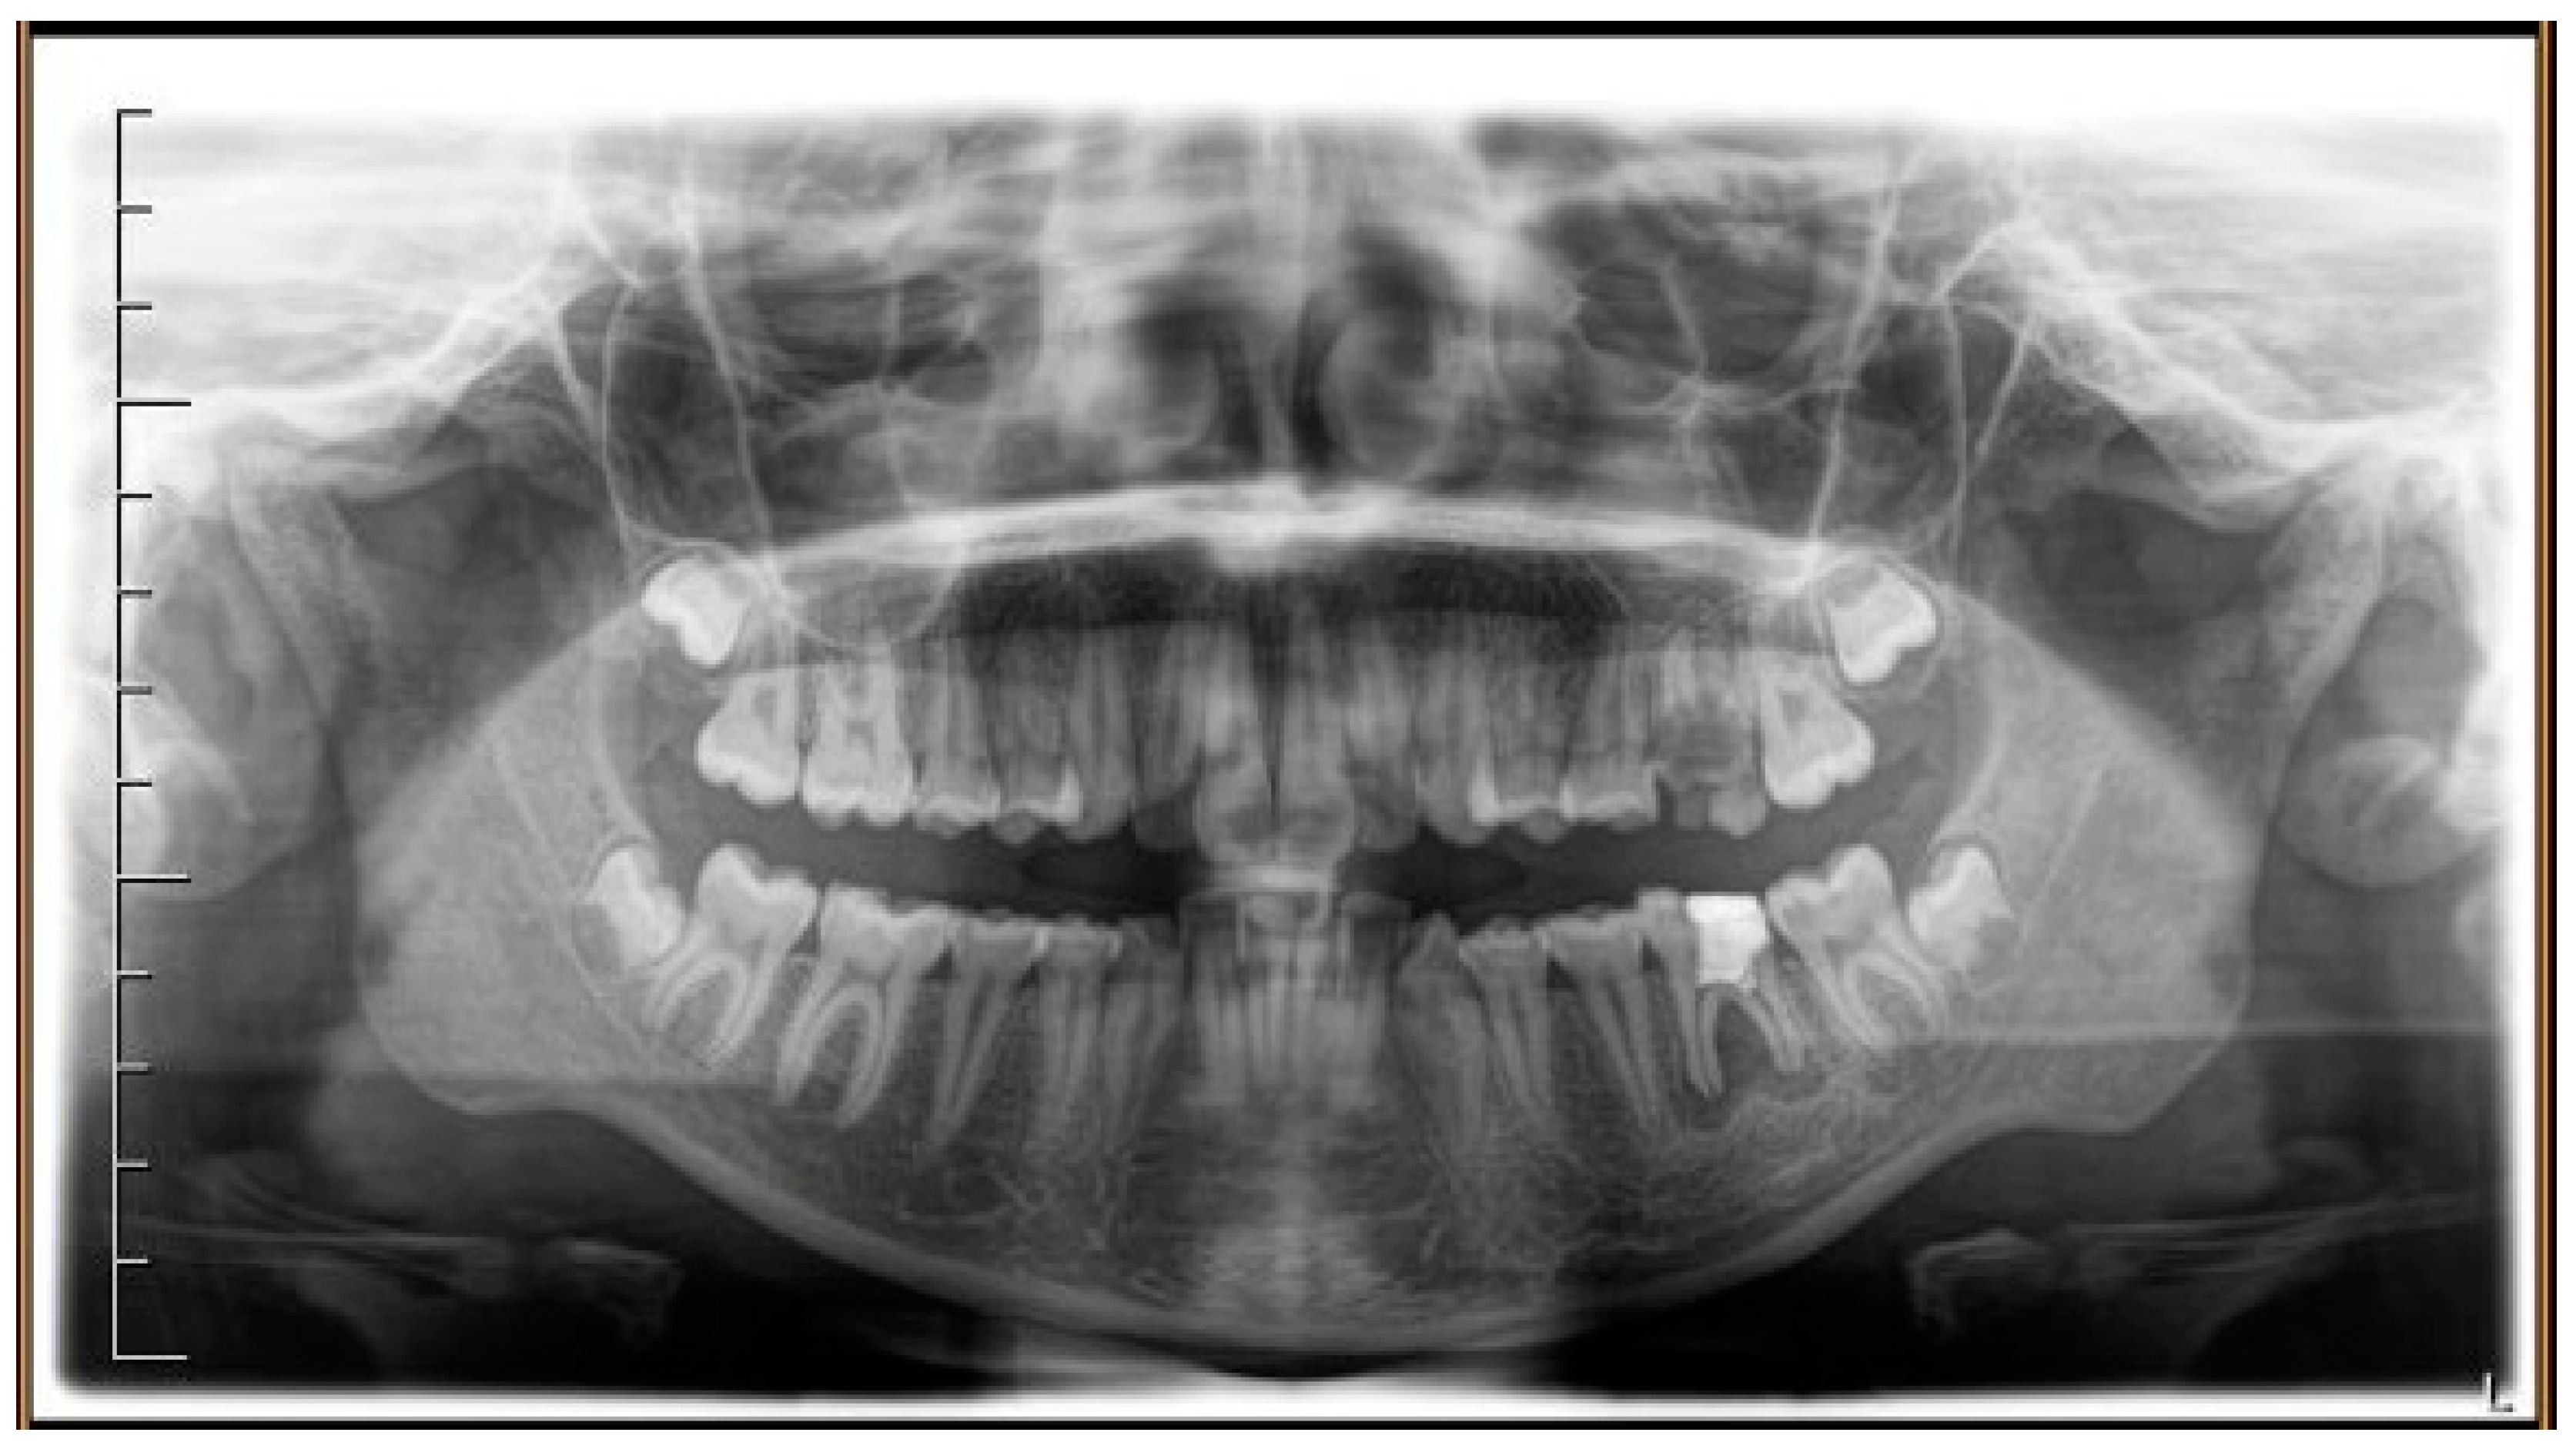

Figure 1.

Pre-treatment radiograph of the patient. The first two left molars appear irreparably compromised by destructive caries.